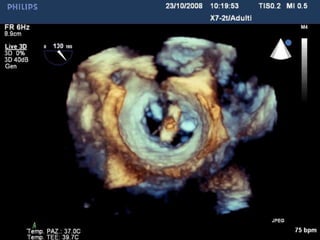

FMR, Log ES 45%, REDO post CABG,

recent AMI, EF 20%, CRT-AICD

• Before treatment • After mitraclip

• The patient was transferred from ICU to the general ward in day 1 and

discharged home 4 days after the procedure

• At 1 year the MR reduction is stable with mild residual MR, reduction of LV

volumes, and the patient is in NYHA class I